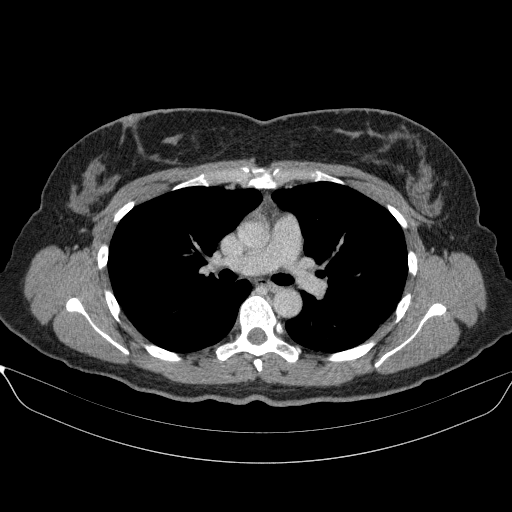

Generated VENOUS CT scan (A→B translation)

No window - Raw intensity values

Native→Venous Translation Metrics (Generated Venous vs Real Venous)

Targeted Slice 70 - Network-Normalized Analysis (Generated vs Real Venous)

0.231

SSIM Score

0.718

RMSE

0.667